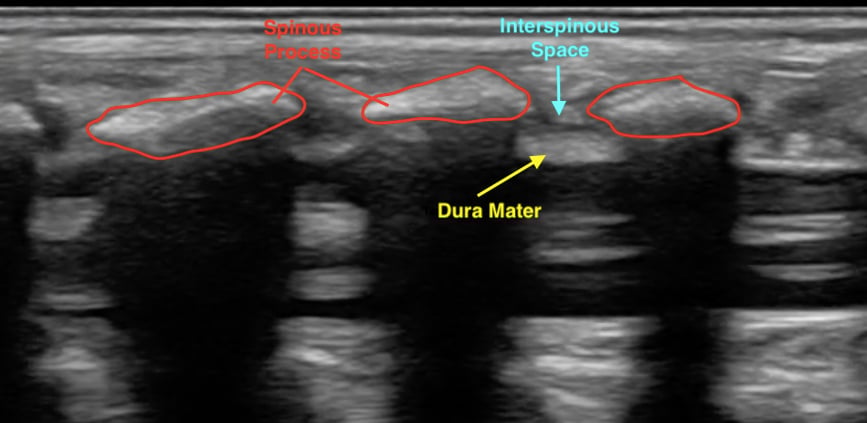

- The ligamentum flavum, dura mater, epidural, and subarachnoid spaces can also be identified using ultrasound.1,6 These additional structures are easier to visualize in young children as bones are not yet calcified.4,6 (Video 1)

- Figure 4. Normal spinal anatomy (pediatric)